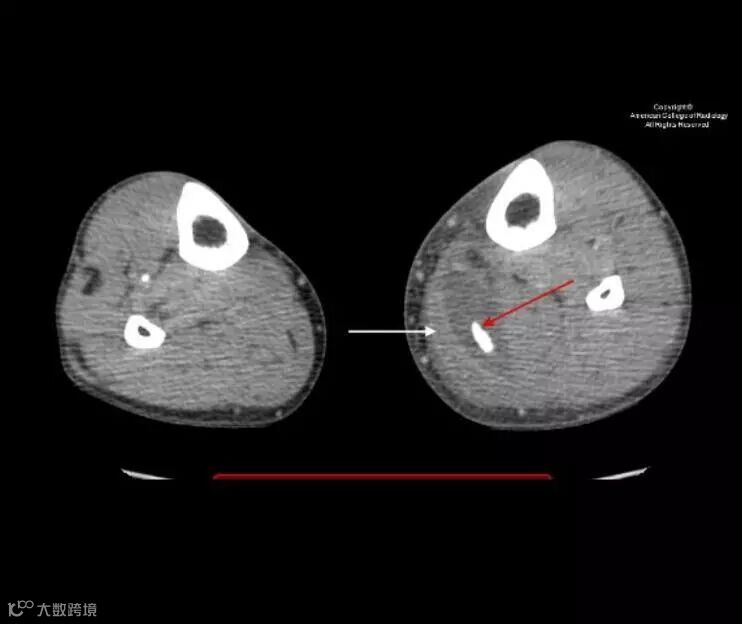

Sagittal reformatted CT image of the left lower extremity demonstrates a cystic structure originating posterior to the medial femoral condyle (white arrow) and extending into the calf soft tissues. There is a calcified body (red arrow) within the inferior aspect of the cyst.

Axial CT image at the level of the mid calf demonstrates a calcified body (red arrow) within a cystic structure deep to the medial head of the gastrocnemius muscle (white arrow).